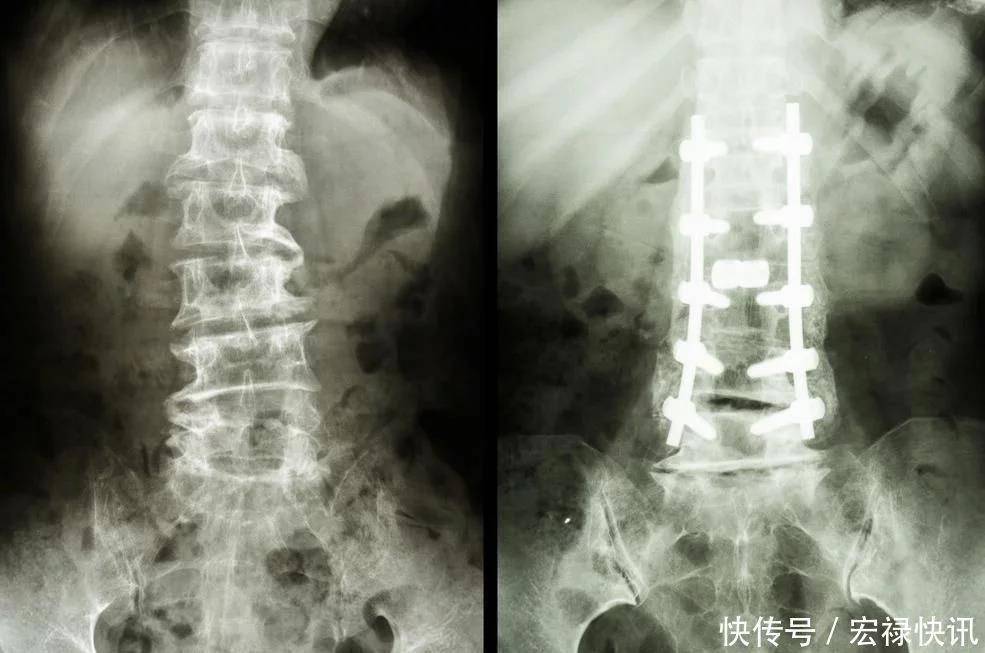

老年人容易出现骨质疏松,因为钙的大量流失导致身体大不如从前。骨质疏松就是我们常常说到的骨质疏松症,因为很多原因导致的骨骼发生病变。尤其是年龄越大的老人家,身体机能大不如年轻的时候,会导致很多的体内物质